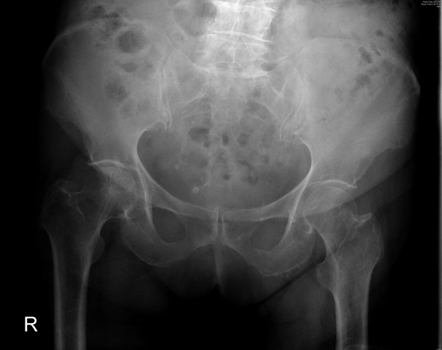

Outras investigações